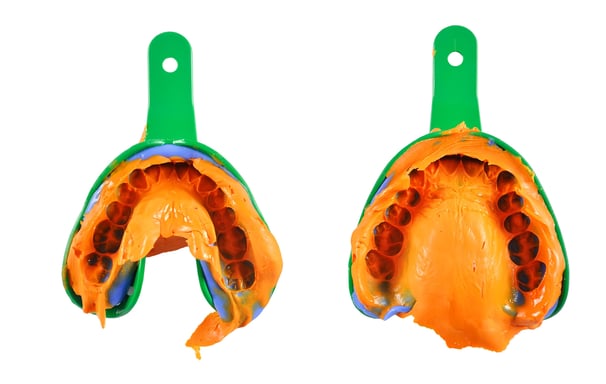

Se utilizan materiales especiales para crear moldes precisos de los dientes y las encías. Estas impresiones son esenciales para fabricar prótesis y restauraciones personalizadas.

Toma de impresiones dentales